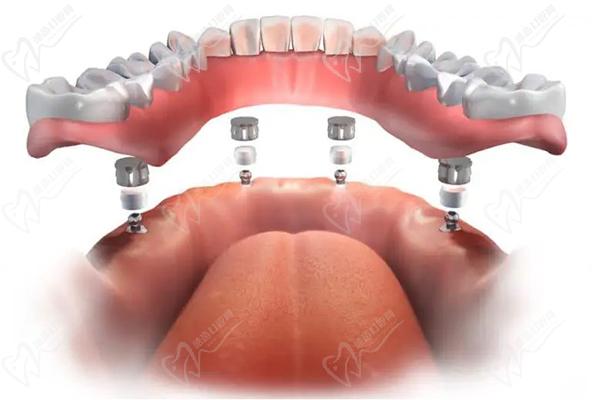

第三步:种植牙

接下来,医生会在必要的位置上植入种植体。这些种植体充当人工牙根,用于支撑和固定新的牙齿。采用数字化智能种植技术,上下牙颌各仅需要4-6颗植体就能恢复半口牙14颗牙齿。